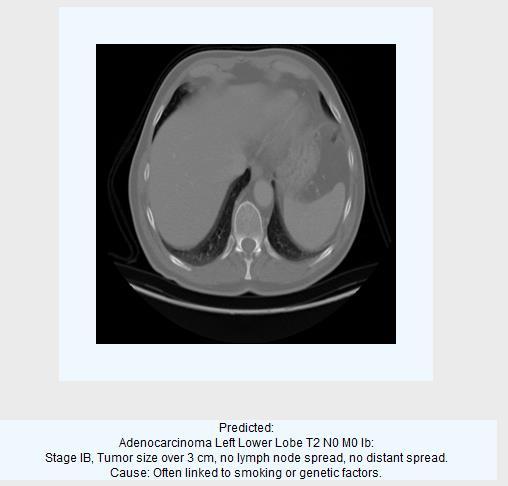

2.3.3Classification output images:

Predictedascancercell-adenocarcinoma